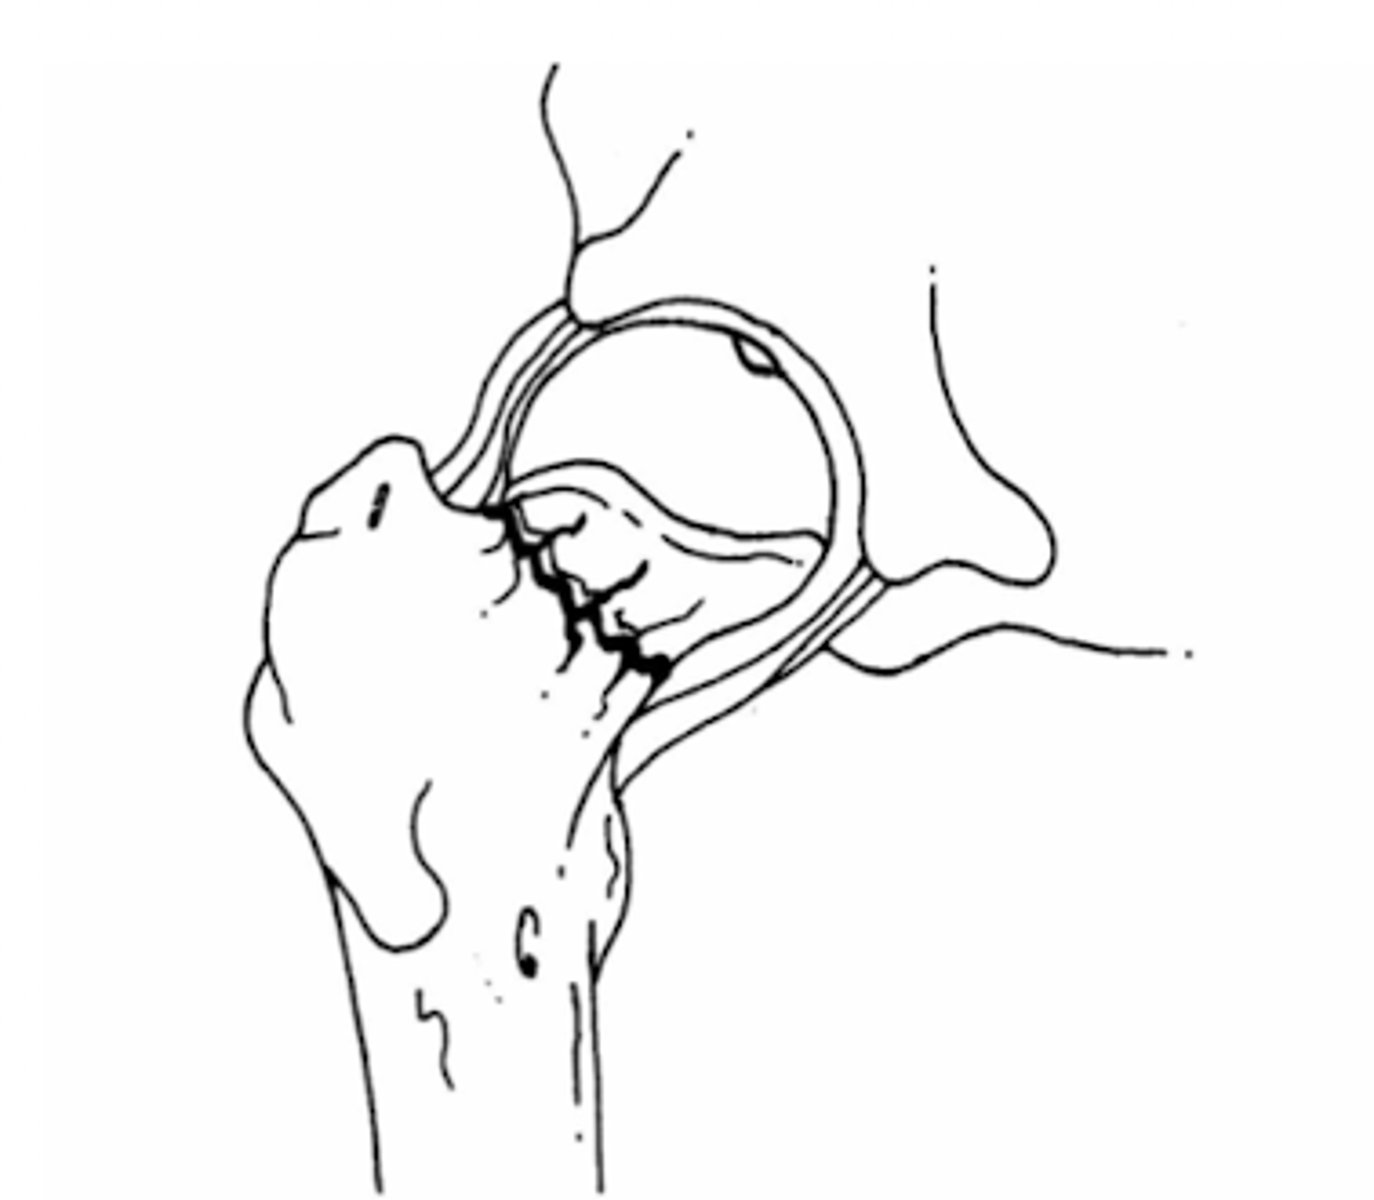

gardens I fx

intercapsular fx